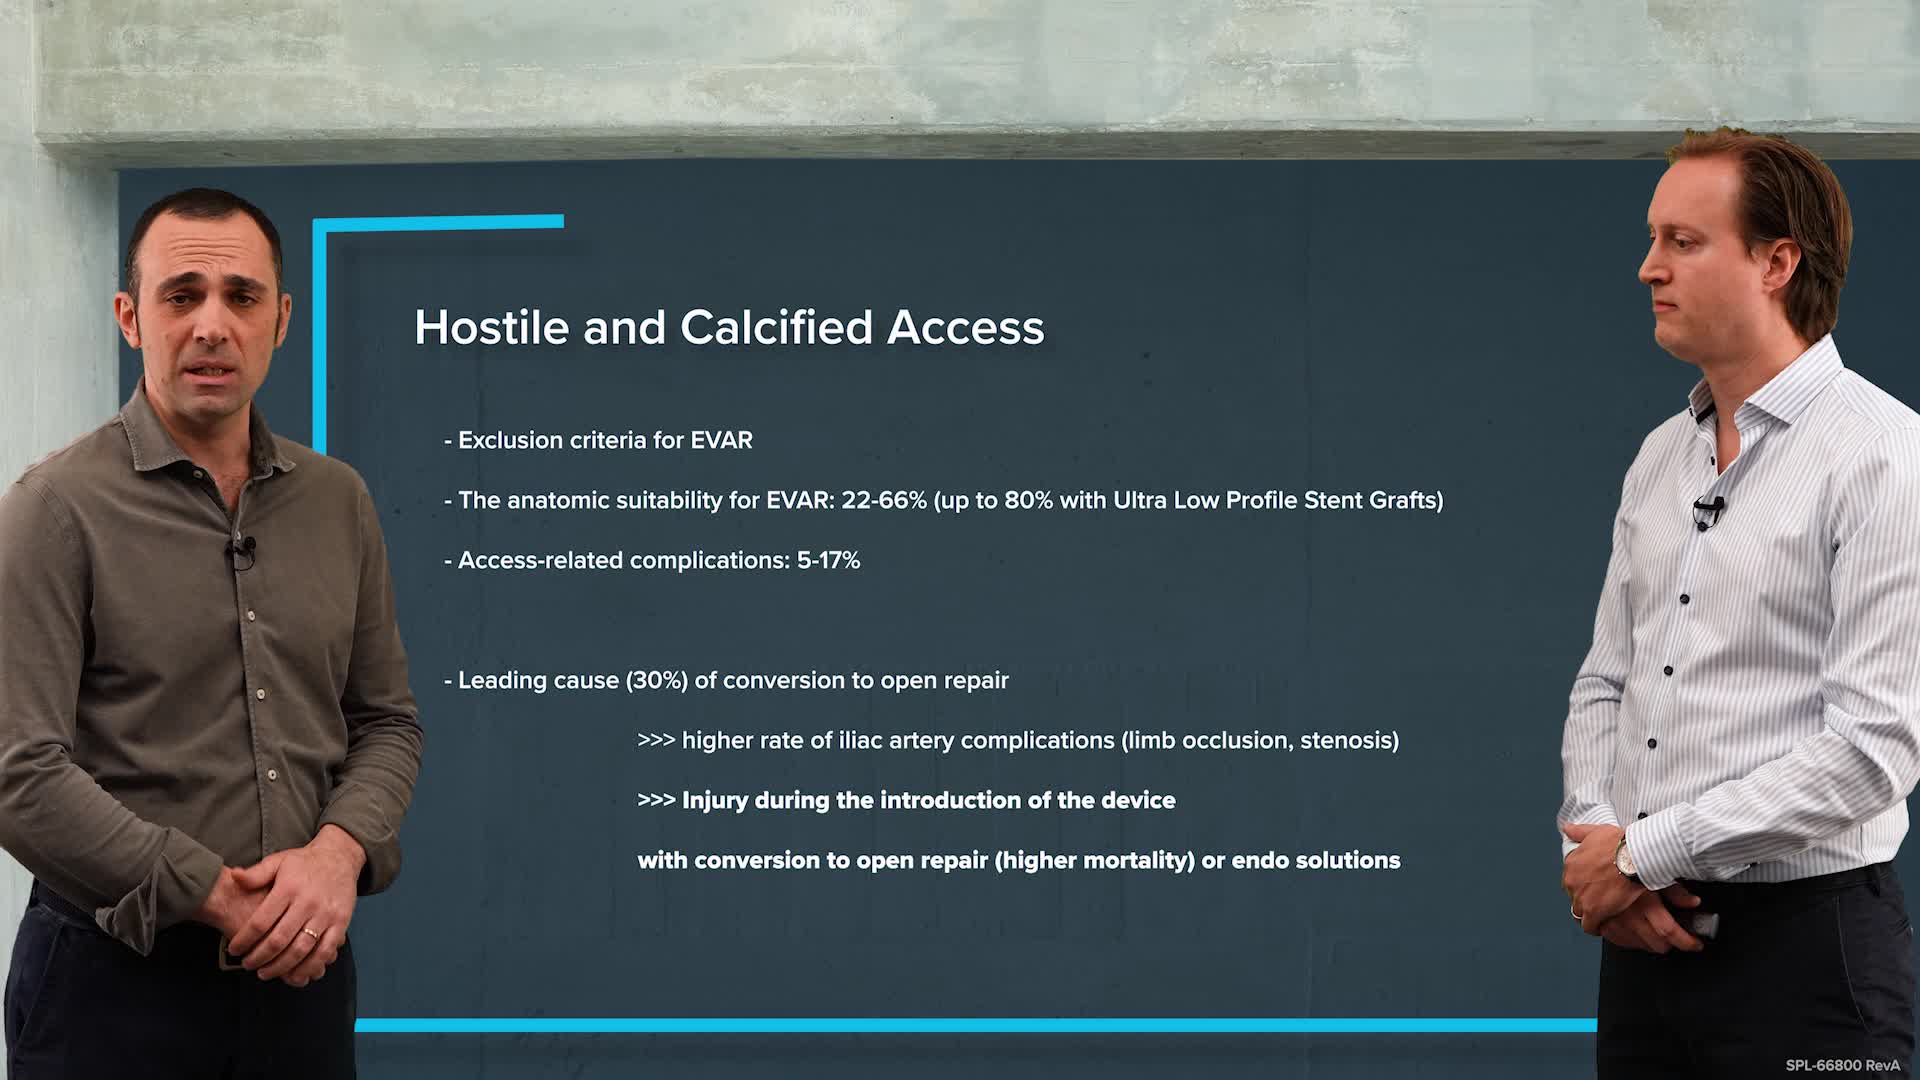

Peripheral IVL learning resources

IVL cracking the calcium conundrum in PAD

Peripheral IVL from the Renals to the Toes